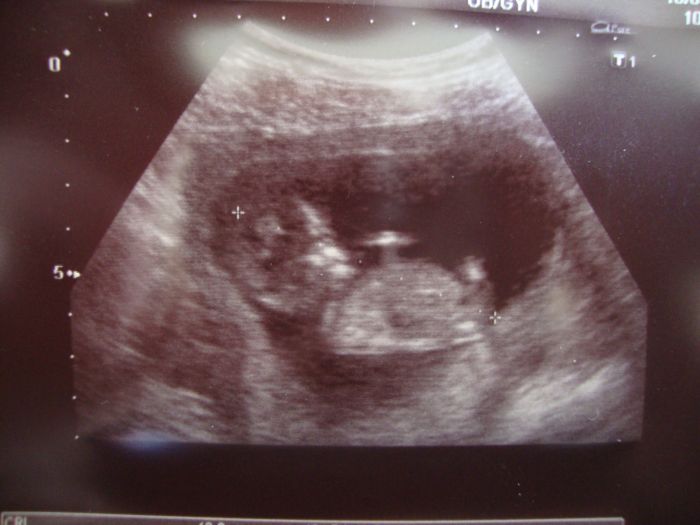

Ahojky holky,tak na ultrazvuku vše v pořádku mimi už má 6,3 cm a je neuvěřitelně akční. podle ultrazvuku jsem 12+5,takže je ted ze mě ta nejštastnější ženská na světě.Jinak Janino 13 tak to jsme stejně mladé:-))).A jedno foto naší modelky nebo modela:-)))

Květo fotečka je nádherná, je dobře že takhle prospíváte